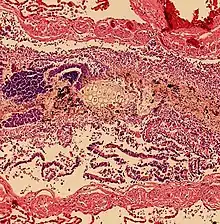

Acid-related

Pulmonary aspiration of acidic material (such as stomach acid) may produce an immediate primary injury caused by the chemical reaction of acid with lung parenchyma, and a later secondary injury as a result of the subsequent inflammatory response.[2]

Bacterial

Pulmonary aspiration may be followed by bacterial pneumonia. Community-acquired aspiration pneumonia is usually caused by anaerobic bacteria, whereas hospital-acquired aspiration pneumonia is more often caused by mixed flora, including both aerobic and anaerobic bacteria.[2]